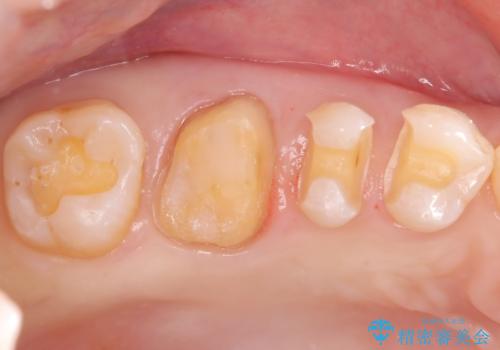

- 左上奥歯に入っている金属の詰め物(メタルインレー)の見た目を改善したいという主訴でご来院されました。お口の中の金属をなくしたいという患者様のご希望を踏まえ、天然歯に近い色と質感を持つセラミックインレーに交換する治療計画を立案。これにより、見た目の改善だけでなく、金属アレルギーのリスクを排除したメタルフリーの環境を実現することを目指しました。

治療では、まず古い金属のインレーを慎重に取り外しました。金属の下に隠れていた虫歯の再発がないかを確認し、歯を丁寧に形成。その後、精密な型取りから患者様の歯の色に合わせたオーダーメイドのセラミックインレーを作製しました。セラミックは、自然な光の透過性を持つため、周囲の歯と区別がつかないほどの美しい仕上がりとなります。適合性の高いセラミックインレーを装着することで、再発のリスクを抑えつつ、長年のコンプレックスだった銀歯がなくなり、笑顔でも気にならない自然な奥歯を取り戻していただけました。